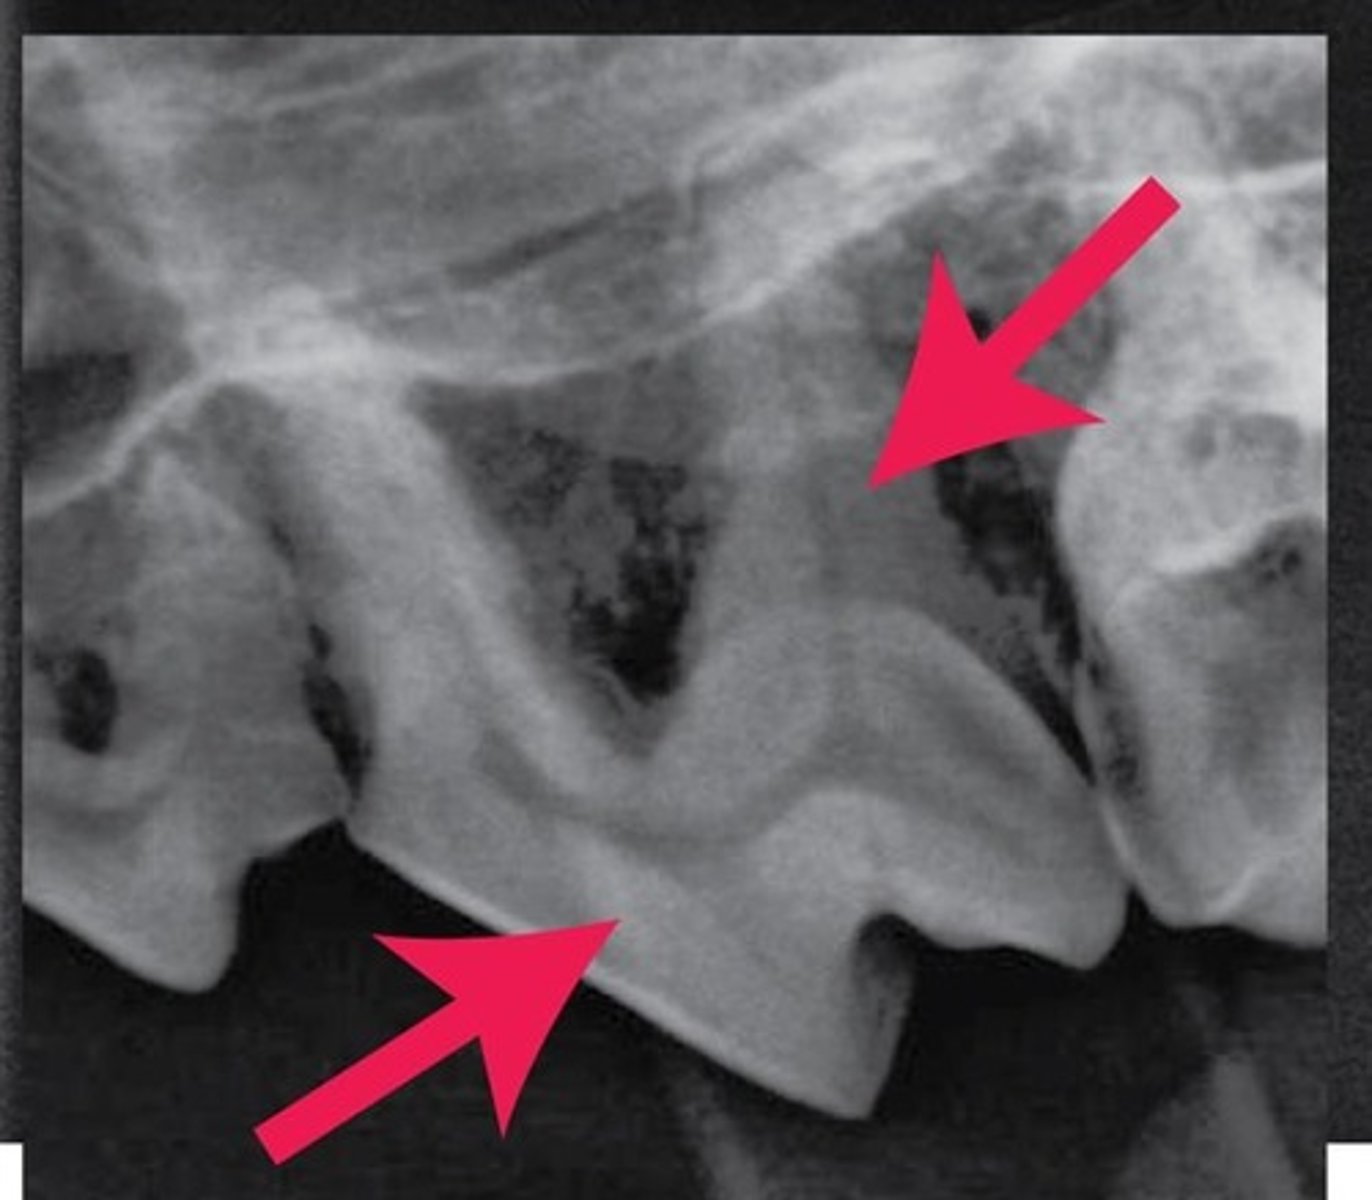

Crown

Identify the part of the tooth encircled.

Root

Identify the part of the tooth outlined.

Neck

The red-hashed line represents what general part of the tooth?

Enamel

What compound covers the external part of the tooth outlined?

Cement

What compound covers the external part of the tooth outlined?

Sockets

Term for the bony "openings" in the mandible and skull that the roots fit into

periodontal ligament

Term for the specialized structure that fastens the root of the tooth into its SOCKET.

Dentin

The arrows are pointing to what substance that makes up the bulk of the internal tooth, deep to the enamel and cement?

dental cavity

pulp

The arrow is pointing to what "space" found within the tooth?

Also, what is the term for the "substance" found within this space?

vessels

nerves

lymphatics

What important "structures" are found in the pulp?

premolars

molars

multiple roots

What type of teeth are the most difficult to extract?

Why?